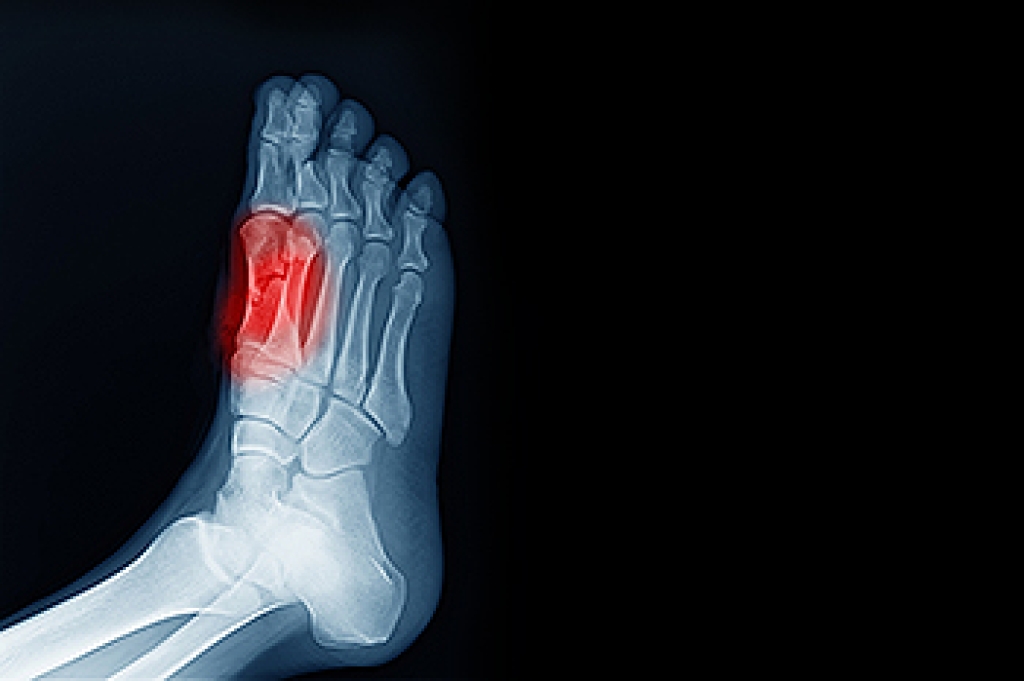

- Stress fractures can occur from overtraining, lack of calcium, or even your running style.